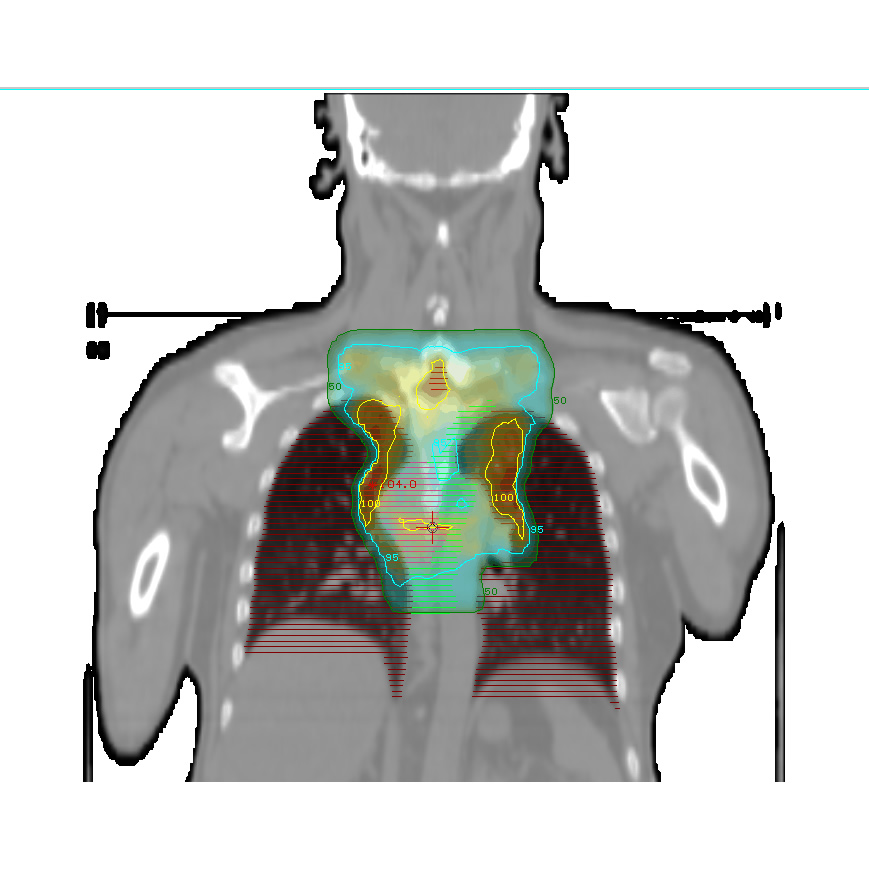

Radioterapia tridimensional conformada (RTC3D)

Es una técnica que se utiliza para el tratamiento radiante de diferentes patologías. Permite conformar la dosis mediante bloques de protección o colimadores multiláminas y de esta forma, delimitar los campos de tratamientos y las incidencias angulares de los mismos. Esta conformación de la dosis, permite brindar las dosis necesarias en los volúmenes blanco (tumor y/o áreas comprometidas), minimizando la dosis en los órganos sanos (OAR). Esta técnica requiere la utilización de imágenes tomográficas específicas para radioterapia necesarias para la planificación de tratamiento en un sistema computarizado (TPS). Se utilizan, también, imágenes de tomografía y/o resonancia magnética y/o PET-CT pre operatorias, para realizar fusión de imágenes en caso de ser necesario. Con estas herramientas, se delimitan los volúmenes de tratamiento así como también los órganos sanos en el sistema de planificación. Una vez, obtenido el plan de tratamiento, es evaluado por un equipo profesional de médicos, físicos y dosimetristas para llevar a cabo la aplicación del mismo en el paciente.